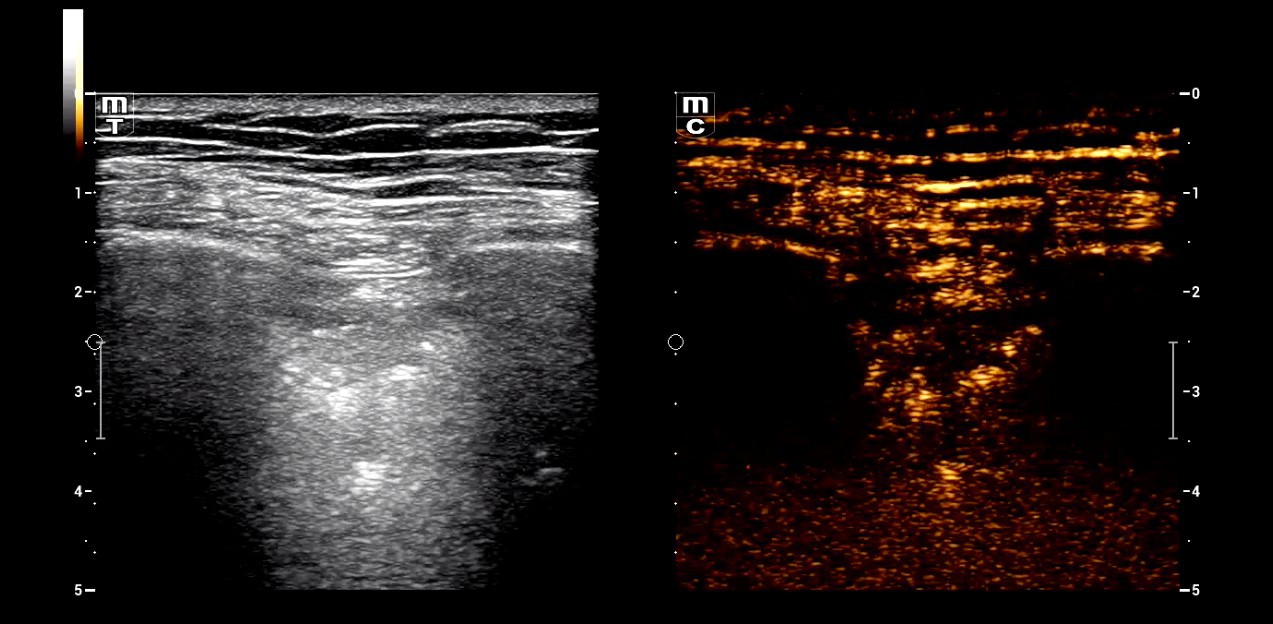

DarÞber hinaus sch?tzt Seibel auch die hervorragende Bildaufl?sung im Nahfeldbereich. Als erfahrener An?sthesist wird er zuweilen auch schmerztherapeutisch t?tig und nutzt das Ultraschallbild, um periphere Nervenblockaden zur postoperativen Schmerztherapie punktgenau zu platzieren. Dabei brauche es ?eine gute Qualit?t auf der Linearsonde, um die Injektionsnadel sicher ans Ziel zu fÞhren.â